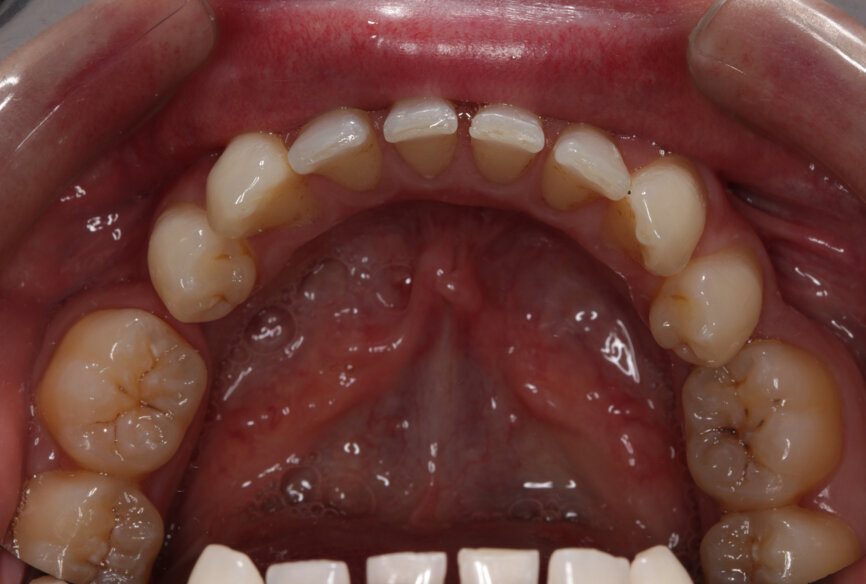

Fig. 17: Post-treatment upper occlusal view

Fig. 18: Post-treatment lower occlusal view